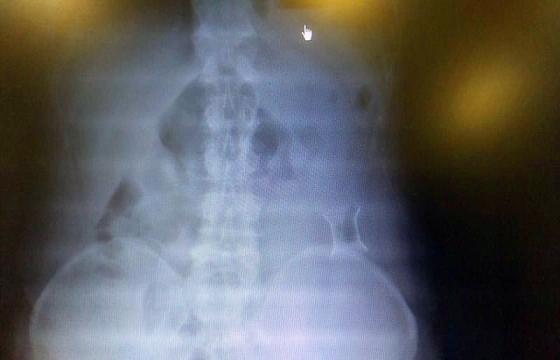

受試患者在結(jié)腸端端吻合術(shù)中,使用我司新研制產(chǎn)品達(dá)到了理想的預(yù)期效果。患者術(shù)后7天、14天X光片顯影,可降解腸道支架均能按研制設(shè)計的預(yù)期時間節(jié)點(diǎn)保持應(yīng)有強(qiáng)度,術(shù)后21天X光片顯示可降解腸道支架已完全破碎,并排出體外。在整個試驗(yàn)過程中,病患無任何不良反映,耐受良好。